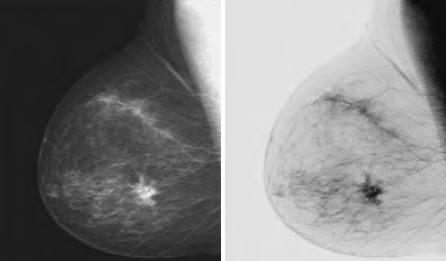

L = Largest gray level in an image. The negative transformation is suited for enhancing white or gray detail embedded in dark areas of an image, for example, analyzing the breast tissue in a digital mammogram.

Image source: Slideshare.net